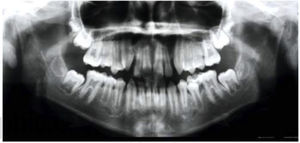

Análisis radiográfico. Se diagnostica clase I esquelética e hiperdivergencia (Figura 3). En la radiografía panorámica (Figura 4) se puede observar la presencia del segundo molar deciduo derecho y el inadecuado paralelismo radicular.

En la radiografía lateral de cráneo, se mantiene la clase I ósea, observamos hiperdivergencia y ligero cambio dental comparado con los estudios de progreso. En la radiografía panorámica se observa un aceptable paralelismo radicular y terceros molares en formación (Figuras 12 y 13).